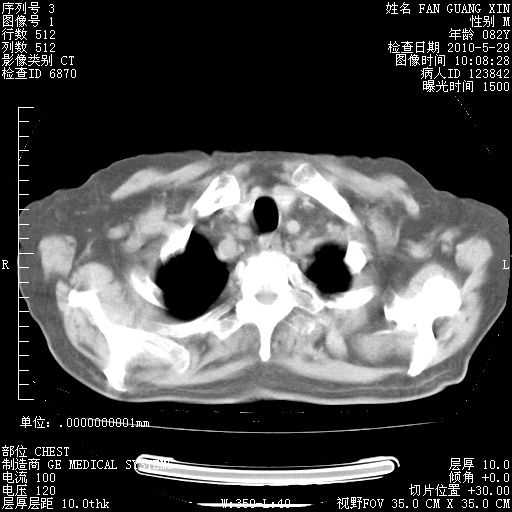

治疗3周后的肺部CT纵隔窗

再治疗10天后的肺部CT 纵膈窗